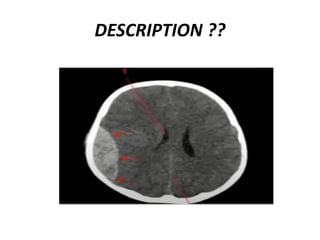

DESCRIPTION ??

LÉSIONS EXTRA AXIALES